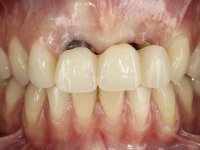

Female patient, 30 years old, non-smoker. The patient appeared in consultation after orthodontic treatment and placement of an implant at tooth site 2.1. Teeth 3.7, 3.6 and 4.7 had root canal therapy and teeth 1.5, 2.5, 2.6 and 4.5 had undergone extensive restorations. Patient had a thin periodontium and showed a satisfactory oral hygiene. After surgical exposure of the implant, it proved to be positioned improperly. Prosthetic rehabilitation of the implant proved impossible by adopting acceptable aesthetic criteria. The patient carried an acrylic temporary crown on a stump screwed as a fallback solution for six years, as she had not accepted the offer to remove the implant. After this time, patient returned to consultation with an abscess in tooth 1.1. After analyzing the situation, it was verified that teeth 1.1 and 2.2 had indicated extraction and the implant should be removed or submerged.

In the initial phase, it was proposed to the patient to perform the surgical implant exposure and after clinical evaluation, make prosthetic decisions. Once the healing screw was placed and the soft tissues were healed, an inadequate position of the implant was found. In view of the dramatic situation, the patient was proposed to remove the implant and put a new one after tissue regeneration. This proposal was rejected by the patient, who suggested temporary rehabilitation of the current implant. A new proposal was then made, to rehabilitate the implant, consisting of a screwed abutment, and on this, the placement of an acrylic crown with coronal and gingival components. After 6 years with the provisional treatment, the patient appeared in consultation with an abscess in tooth 1.1. After clinical and imaging analysis, it was decided to remove teeth 1.1 and 2.2, submerge the implant, place two implants at the site of 1.1 and 2.2 and perform adequate tissue regeneration. Temporization would be done with a provisional 3-element bridge, adhered with a net to the neighboring teeth. After osseointegration, definitive rehabilitation would be done with a 3-element bridge, including zirconia infrastructure and ceramic cover.

The surgical implant exposure and the healing screw placement proved to be a negative surprise regarding its position. Since the proposed removal of the implant was refused, we advanced to its provisional rehabilitation. An open tray impression technique was done, and a screwed abutment with a coronal and gingival component and an acrylic crown were made in the laboratory, using these two components. The provisional crown was placed in the mouth until a final decision was made. Six years passed before the patient returned to the clinic with an abscess on tooth 1.1. The choice to remove teeth 1.1 and 2.2 was made, to create a provisional 3-element bridge with a net to be adhered to the adjacent teeth. Surgery was planned and performed, placing the two implants at the site of 1.1 and 2.2, and the implant at the 2.1 site was cut with the objective of submerging it, while adequate tissue regeneration was performed (Surgical Work performed By Dr. Manuel Neves). During osseointegration, the patient used the fixed provisional bridge. A first impression was made for confection of a zirconia screwed provisional bridge, which worked the soft tissues for twelve weeks. The definitive impression was made with the individualisation of custom impression copings. Final rehabilitation was done with ceramized abutments, and also a bridge with zirconia infrastructure and ceramic cover. Due to the inclination of the implant placed at the site of tooth 1.1, the bridge required cemented fixation.